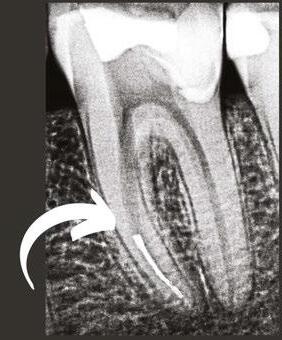

Figure 1: A PA X-ray showing a failed root canal treatment on a lower incisor (left) and the corresponding endodontic microsurgery (right) showing the original oval and missed anatomy of the canal. Courtesy Dr. Bertrand Khayat, Paris, France Dr. Chafic Safi treating a patient at his practice, Centre Endodontique Saint-Laurent, in Montreal, Canada

Traditional endodontic files cannot enlarge the natural cross section of the root in all directions; rather they induce a round shape, leaving large areas untouched and packing debris in the oval extremities.3 This prevents adequate cleaning and disinfection (Figure 1). Moreover, the more a canal is tapered with traditional instruments, the thinner and the weaker the tooth becomes. Traditional rotary instruments have consistently been shown to create dentinal defects and cracks that are suspected to lead to root fractures.4 Even reciprocating techniques create dentinal cracks, without mentioning their debris extrusion into the periapical tissues.5,6